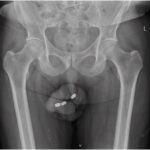

O frentista Gilberto Nogueira de Oliveira, de 39 anos, teve o pênis amputado pela companheira, a cozinheira Daiane dos Santos Farias, de 34. O crime foi motivado por uma traição do homem, que teve caso com a sobrinha da mulher, de 15.

Em momento de vingança, ela prendeu o órgão genital do parceiro em um elástico e usou uma navalha para cortá-lo. Na delegacia, a cozinheira confessou toda a trama e foi presa. Já o homem passou por uma série de cirurgias e ainda não está totalmente recuperado.